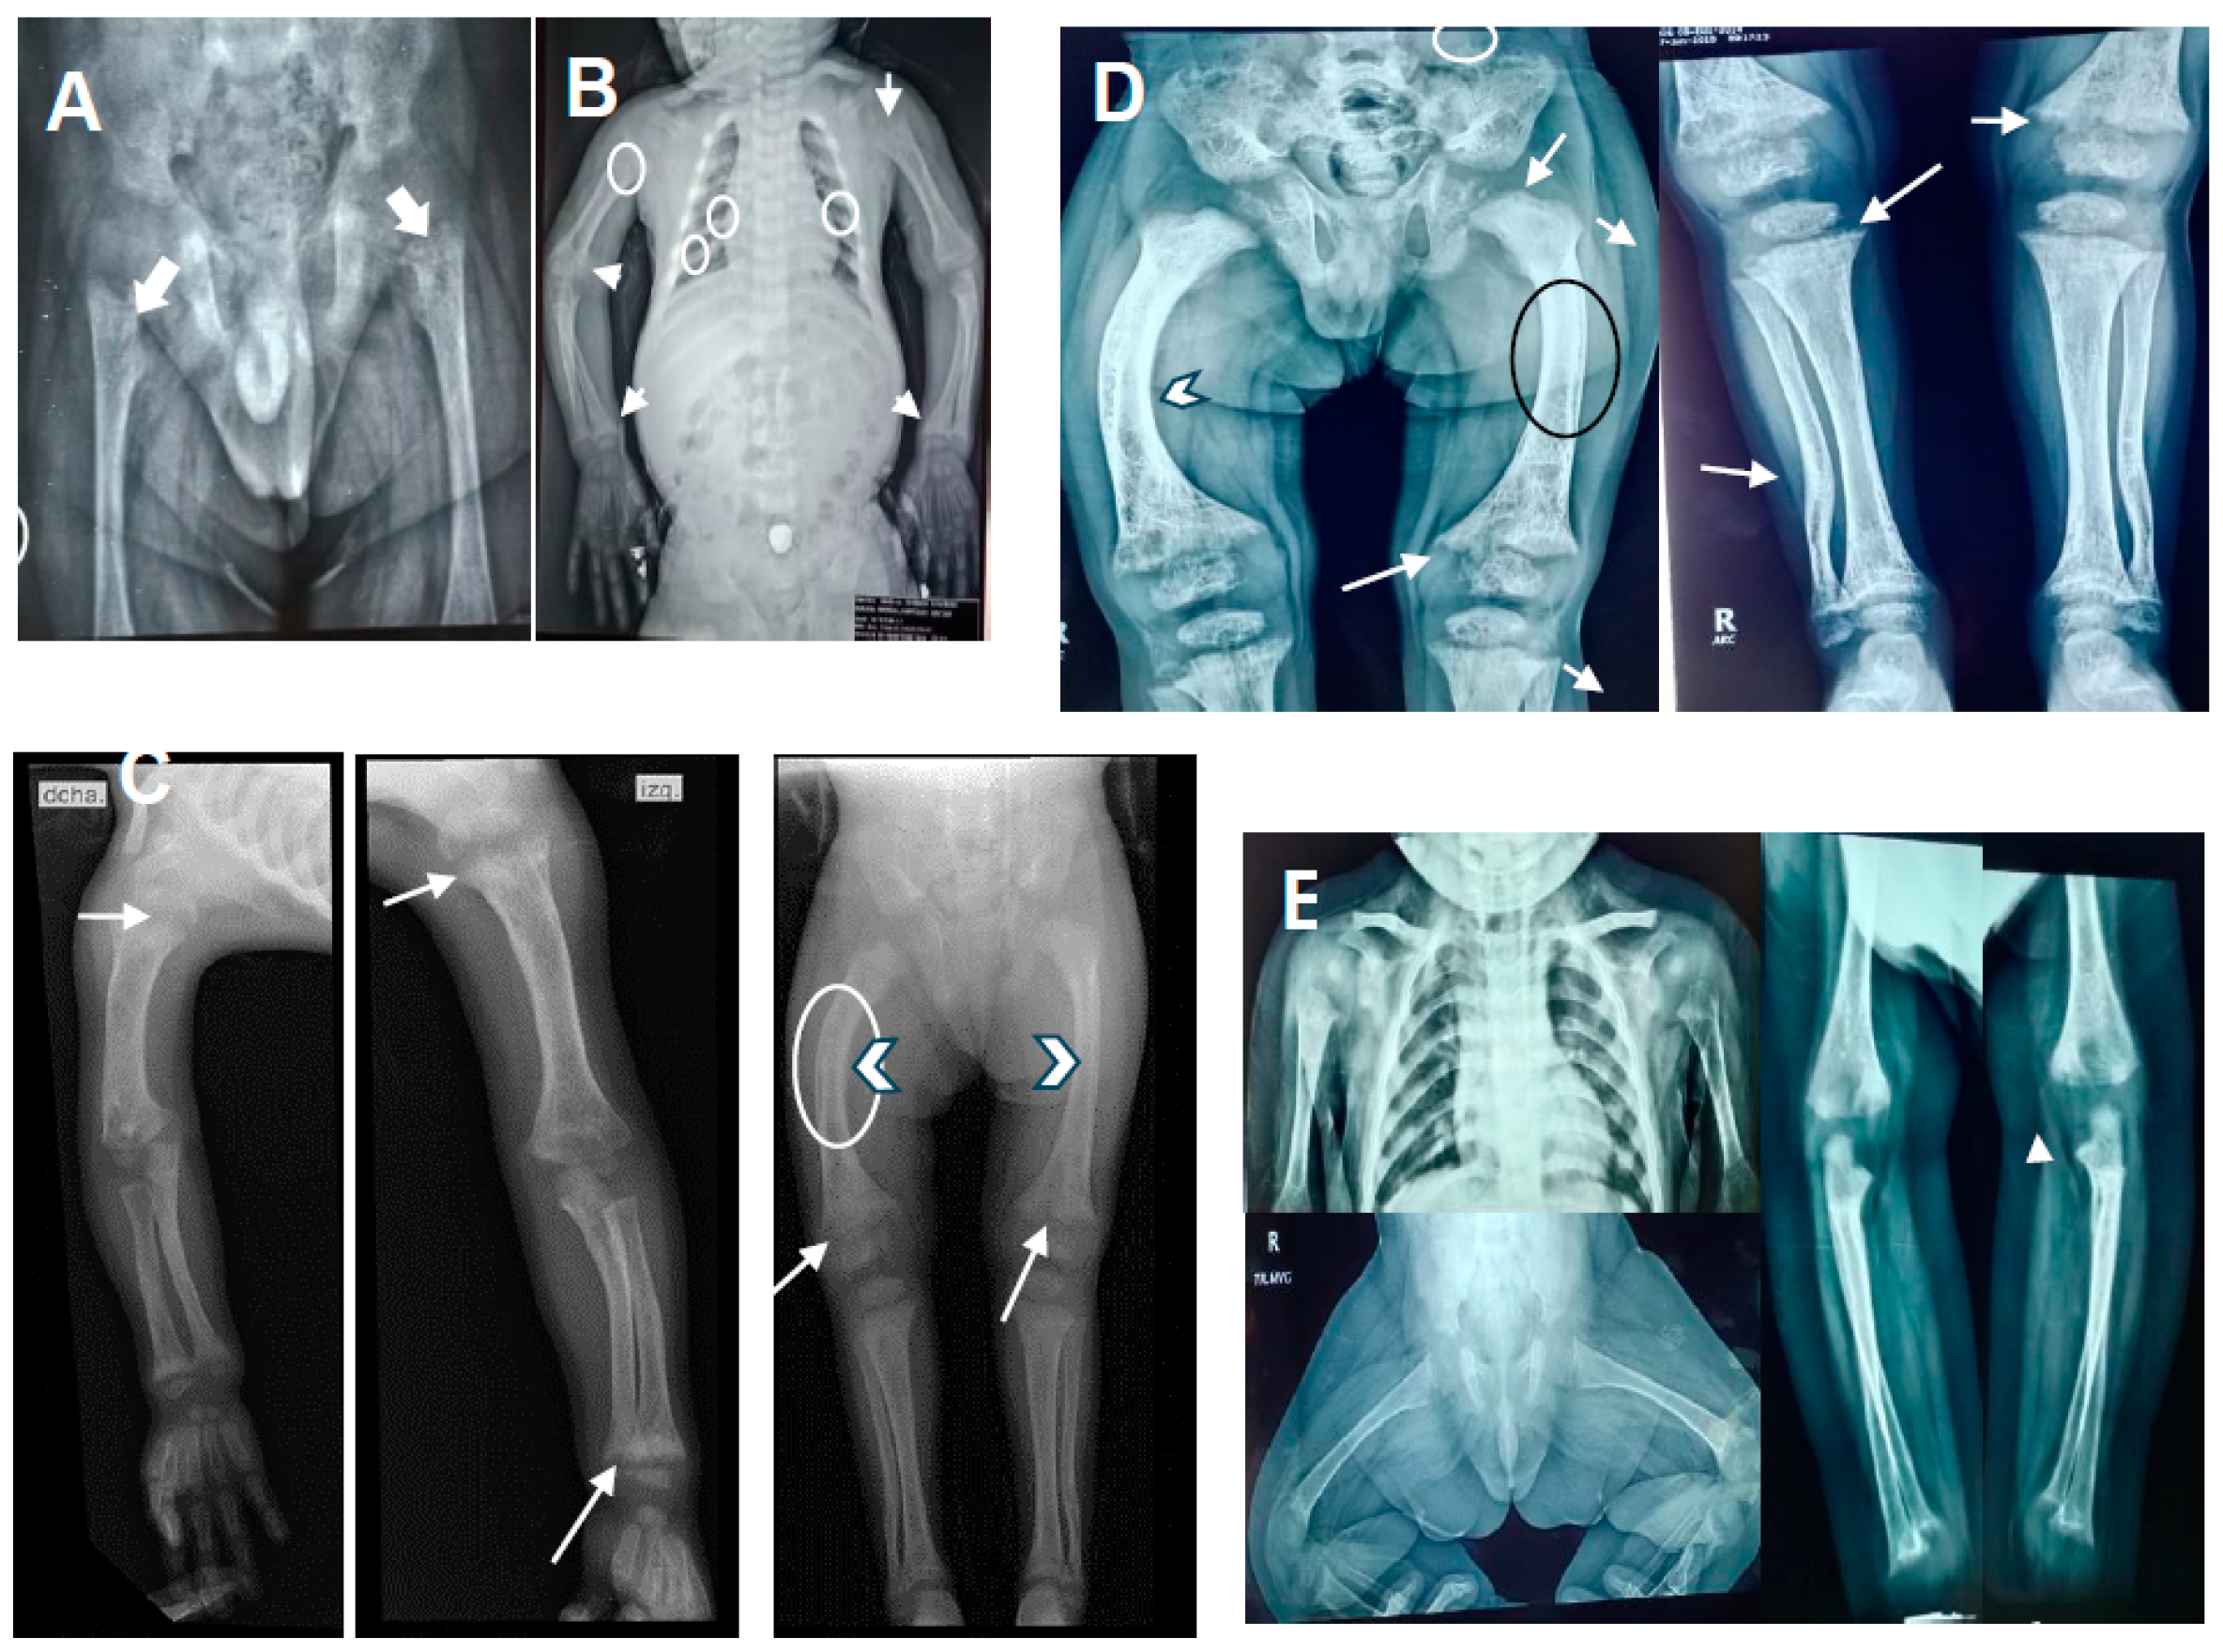

| Case 1 (proband; 13 mo) Case 2 (Brother; 2 mo) | c.227G>A; c.1319_1325dupCCCACCC. c.227G>A; c.1319_1325dupCCCACCC. | 2 8 2 8 | p.Trp76*; p.Phe443Profs*24. p.Trp76*; p.Phe443Profs*24. | Low-normal calcemia, no seizures, fractures, severe growth retardation, sclera gray, café-au-lait spots, frontal bossing, mild medial facial hypoplasia, and pectum carinatum. Gray sclera. | Good biochemical response, partial to rickets, and bad growth deformity prevention Good biochemical, rickets, growth response, and prevention of deformities | This study |